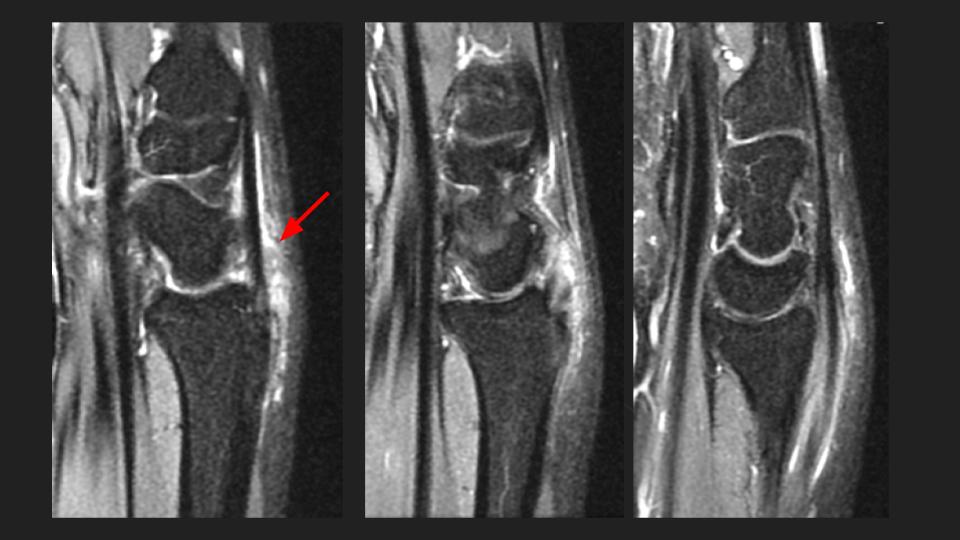

35M 5 months pain, referred to evaluate the scapholunate ligament

Red arrows point to the EPL which appears partially torn proximal to the level of Listers tubercle. On MRI (I wish this were US, I hear you) the distal remnant at the site of intersection with the 1st extensor compartment looks quite attenuated, but I see something passing over ECRL/ECRB with fluid signal between. Is this a complication of neglected proximal intersection syndrome? I have never seen it progress to EPL tear, but apparently there are Italian radiologists (see attached abstract) who have. Reference article.

extensor pollicis longus tendon ( RID2378 )